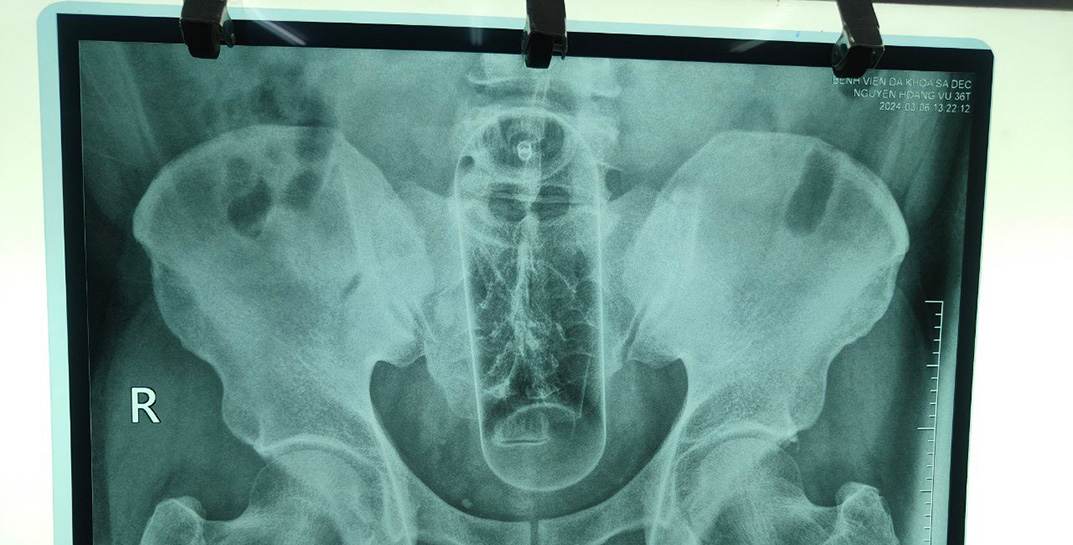

По словам медика, лидеры рейтинга инородных предметов в анальном проходе — секс-игрушки. Но находились и совсем уж экзотические вещи. В ТОП нетривиальных находок проктолога попали скалка, толкушка для картофельного пюре, граненые стаканы, рюмки, морковка, огурец и даже электрическая зубная щетка без насадки.

Среди наиболее частых объяснений пациентами, откуда в анусе предмет, лидирует — «выходил из душа, поскользнулся и упал на…». Кроме того, многие мужчины говорят, что, по совету уролога, использовали предмет для массажа предстательной железы. Единицы пациентов признаются, что пытались получить «новые ощущения».